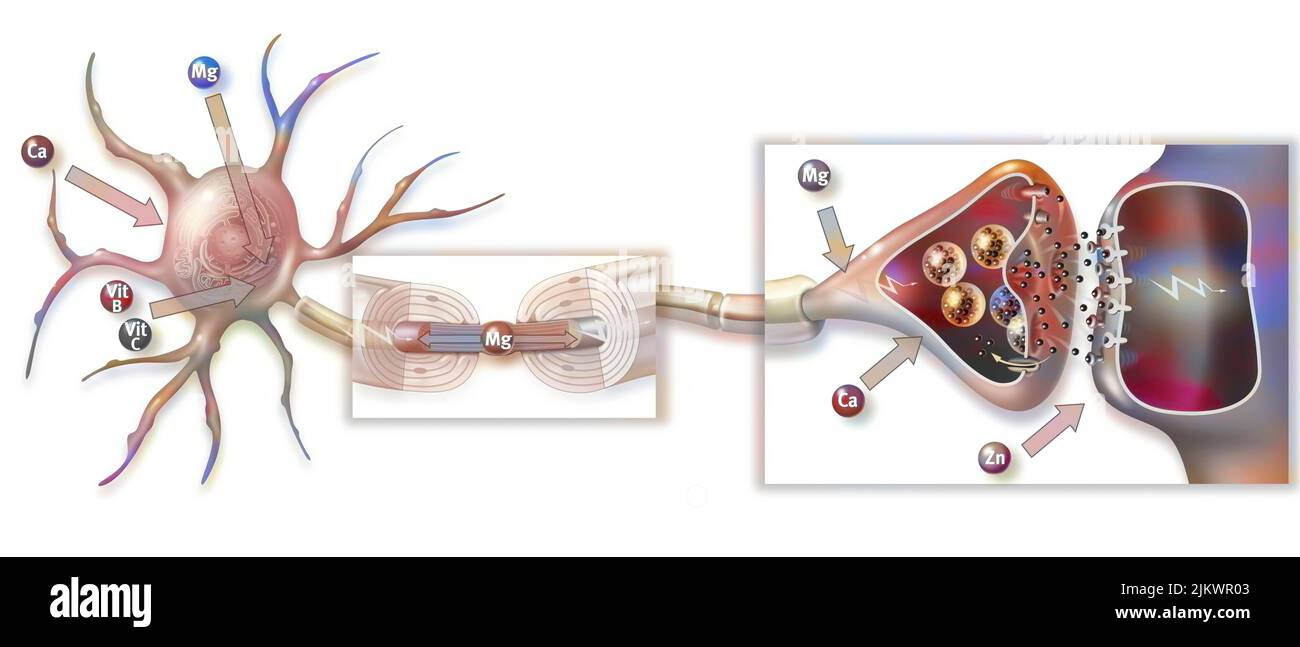

RF2JKWR03–Action des sels minéraux et des vitamines sur la transmission des impulsions nerveuses aux synapses.